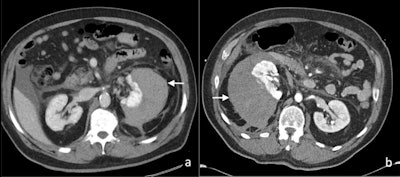

Axial contrast-enhanced CT images of (A) perinephric hematoma (white arrow), and (B) subcapsular hematoma (white arrow) postextracorporeal shock wave lithotripsy in two patients.

Axial contrast-enhanced CT images of (A) perinephric hematoma (white arrow), and (B) subcapsular hematoma (white arrow) postextracorporeal shock wave lithotripsy in two patients.One of the most common complications of ESWL is the formation of a perinephric or subcapsular hematoma, with an incidence of approximately 4%. The risk of a renal hematoma post-ESWL is significantly increased with increasing patient age, use of a therapeutic dose of low molecular weight heparin and the presence of an untreated urinary tract infection. The resultant compression of the kidney from the perinephric or subcapsular hematoma has been reported to cause systemic hypertension, also known as Page kidney.